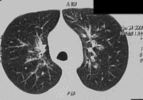

Компьютерные томограммы

Диссеминированное поражение легких